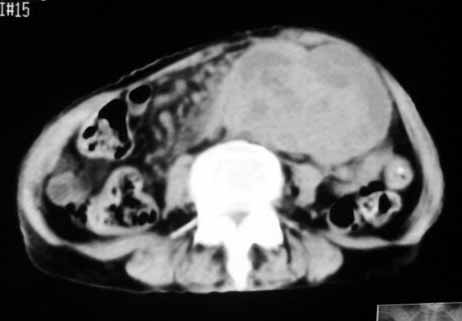

1.中腹部腹主动脉旁可见巨大包块影,其形态似为2个(或分叶),与腹主动脉分界不清,边界较清,其内密度不均匀(稍高、不匀称低密度),腹膜后未见确切肿大淋巴结...性质?考虑腹主动脉瘤可能性大,不排除平滑肌瘤及畸胎瘤可能,建议增强ct;

考虑:1、左侧腹膜后占位性病变(以间叶源性肿瘤可能性大);

脂肪肉瘤,平滑肌肉瘤的可能性大。支持!(本例关键是定位,仔细分析,可以观察到主动脉被包埋于肿瘤内,因此可定位于—来源于腹膜后的实性肿瘤。)

腹膜后肿块侵犯腹主动脉及肠系膜上动脉,肿块密度不均,1来源间叶组织肿瘤,2肠系膜恶性肿瘤可能大,

,因为如果是来源于腹主动脉的动脉瘤的话,长径应该呈梭形.腹主动脉被肿块包埋,考虑来源于小网膜囊的间质瘤